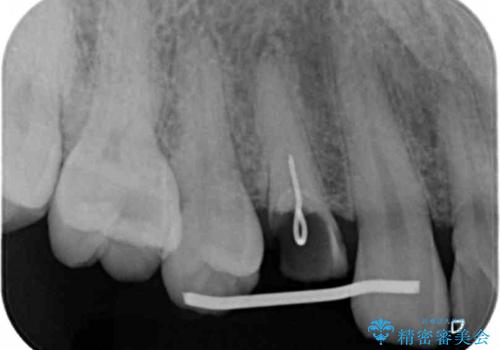

レントゲン画像上で歯茎の深いところまで虫歯になっており、保険治療では抜歯適応になってしまいます。

今回は虫歯の深いところが歯茎のラインにくるまで部分矯正で引っ張り出し、適合の良いかぶせ物を装着しました。

初診時の状態では虫歯が大きすぎて取り切ることができなかったため、まず歯を骨から引きあげて虫歯がしっかり除去できる状態にしました。